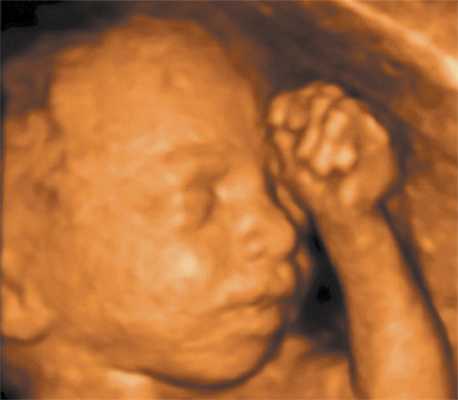

Трехмерное изображение лица плода может также способствовать установлению контакта между матерью и ребенком подобно первому прослушиванию сердцебиений (рис. 1).

Рис. 1. Нормальное лицо плода.